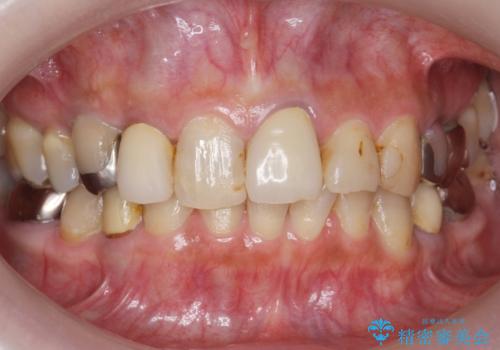

[ 審美歯科 ] ジルコニアクラウンで自然な歯に